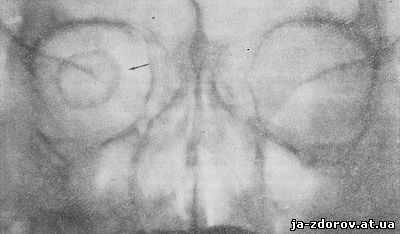

В этой же укладке может быть выполнен снимок одной (правой или левой) глазницы. В таких случаях центр снимаемой глазницы соответствует центру кассеты, и на него отвесно направляют пучок излучения, используя тубус или диафрагмирование пучка излучения с помощью щелевой диафрагмы. Фокусное расстояние—100 см (рис. 88).

Информативность снимка. На снимке хорошо видны вход в глазницу, структура ее стенок, иногда малое и большое крыло клиновидной кости (рис. 89). На снимке в этой проекции могут быть выявлены деструктивные изменения стенок глазницы и инородные тела в ее полости (рис. 90, 91). Для выявления изменений в области верхней стенки глазницы (например, при

диагностике переломов) снимок целесообразно выполнять не в носоподбородочной, а в подбородочной проекции.

На прицельном снимке каждой из глазниц в этой же проекции, как правило, небольшие изменения структуры стенок, а также мелкие инородные тела глаза видны лучше. Такие снимки широко используют в офтальмологической практике (рис. 92).